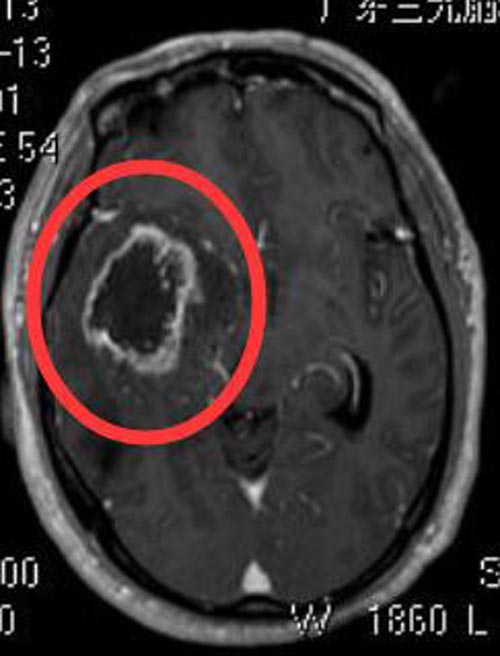

陈爷爷今年62岁,半年前出现阵发性头痛,伴左下肢乏力、恶心,当地医院就诊,未行头颅相关检查及治疗。半月前头痛、左侧肢体乏力进行性加重,转上级医院检查,头颅CT结果:“右侧颞叶巨大占位”。广东三九脑科医院头颅MR检查提示:右侧颞叶占位性病变,范围约为4.9cm×4.7cm×3.7cm,考虑胶质母细胞瘤可能。

▲术前